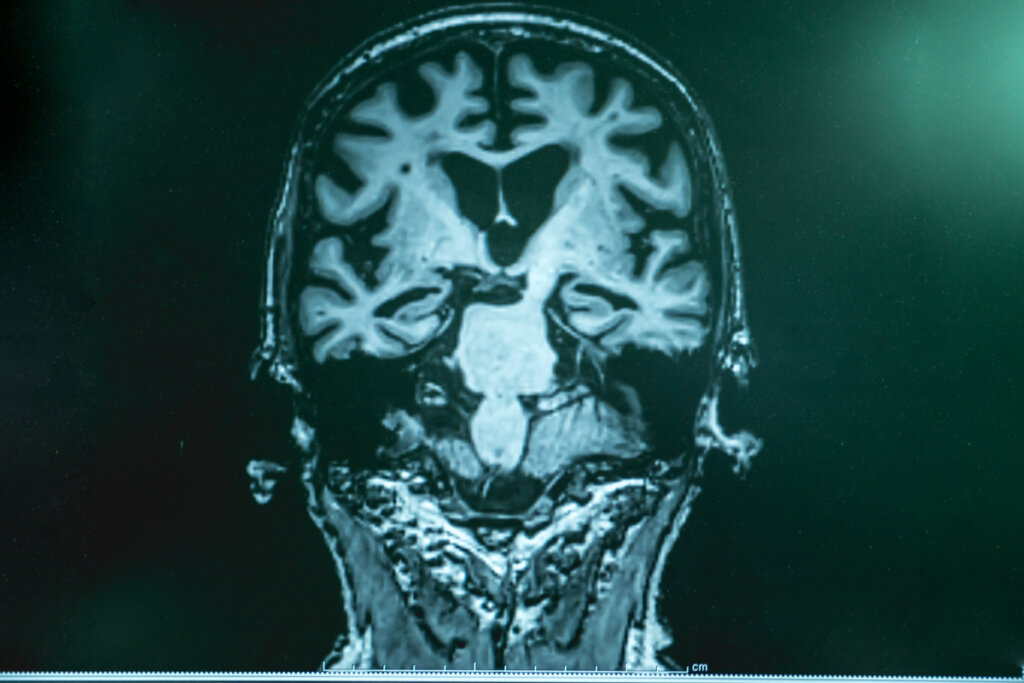

La enfermedad de Alzheimer sigue siendo, en buena medida, un misterio. Se trata de una enfermedad que solo se puede confirmar postmortem y sobre la que todavía tenemos muchas dudas respecto a su origen.

Como hemos mencionado al principio, el origen del alzhéimer no es del todo conocido. Sí se conocen algunas alteraciones fisiopatológicas características de la enfermedad: los depósitos de proteína beta amiloide que acaban formando placas alrededor de las neuronas y las inutilizan, la formación de ovillos neurofibrilares intracelulares y la presencia de proteína tau fosforilada.